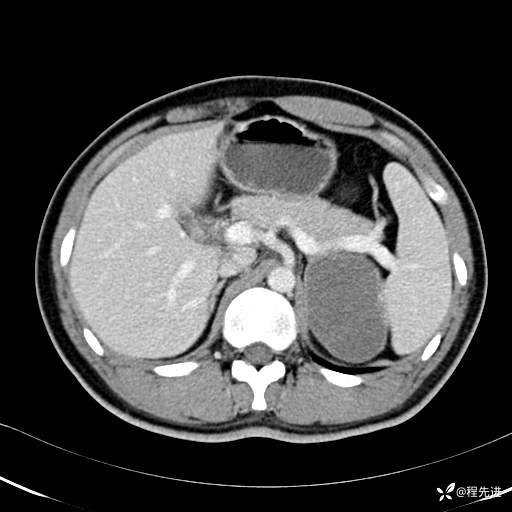

门静脉期: